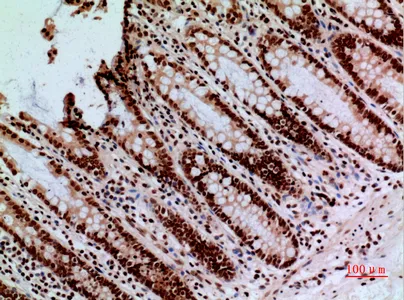

HDC Rabbit Polyclonal Antibody

Cat: APRab11956

Size1:50μl Price1:$118

Size2:100μl Price2:$220

Size3:500μl Price3:$980